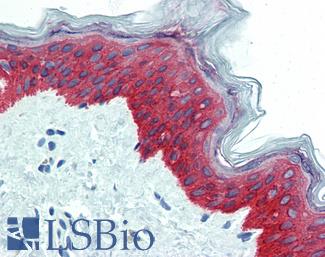

CK14 (KRT14)

Anti-KRT14 / Cytokeratin 14 antibody IHC of human skin. Immunohistochemistry of formalin-fixed, paraffin-embedded tissue after heat-induced antigen retrieval. Antibody LS-B3916 dilution 1:25.